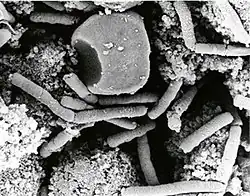

Erreger

Der Milzbranderreger, Bacillus anthracis, gehört zur Gattung Bacillus (sporenbildende, aerobe Stäbchenbakterien) innerhalb der Familie Bacillaceae. Er ist ein etwa fünf bis sechs µm (1 µm = 0,001 mm) langes, grampositives, unbewegliches, sporenbildendes Stäbchen, das in Körperflüssigkeiten kurze, in der Kultur längere kettenförmige Verbände bildet („Serpentinen“- oder „Medusakopf“-Form). Im Tierkörper ist die Bakterienzelle von einer deutlichen Kapsel (bestehend aus D-Glutamat) umhüllt, während in der Kultur in der Regel keine Kapselbildung erkennbar ist. Außerhalb des Tierkörpers, in Anwesenheit von Sauerstoff und bei Temperaturen von 12 bis 43 °C, bilden sich Sporen (Dauerformen), deren Größe etwa 0,5 bis 1,2 µm beträgt.